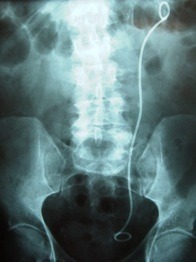

En fait tu auras une anesthésie locale (au gel) et la sonde sera retiré sous endoscopie.

L'endoscope sera inséré au niveau de l'urètre et un system de pince viendra tirer la sonde JJ vers l'extérieur.

Ce geste dure moins de 5 min, si la sonde glisse toute seule et c'est complètement indolore!

Normalement il y a un systeme de valve sur l'uretère à l'entrée de la vessie.

Comme la sonde est en place cette valve est constament ouverte ... donc l'urine remonte dans l'uretère. Ca donne de drole de sensations.

De plus tu as vu la forme de cette sonde ... pas très glamour ... elle pèse sur les parois du rein et de la vessie.